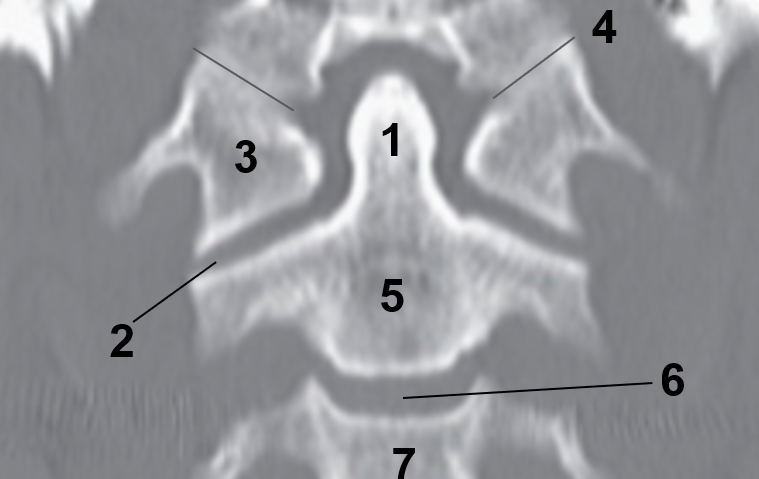

1?

Nasal Bone

2?

Maxillary Sinus

3?

External Acoustic Meatus

4?

Pons

5?

Cerebellum

6?

Mastoid Air Cells

7?

Mandibular Condyles

8?

Sphenoid Bone

9?

Maxillary Bone